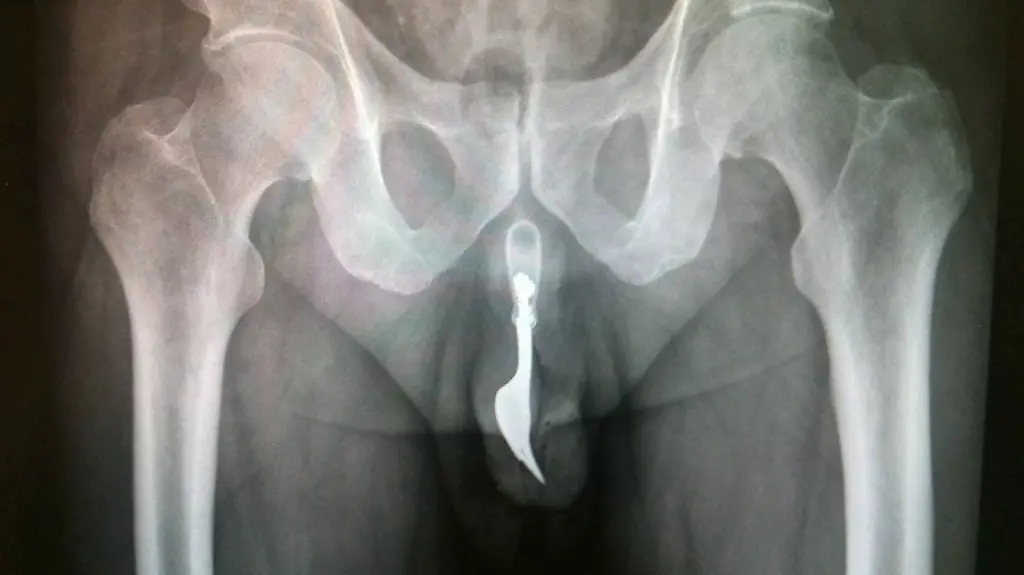

Weil er sich selbst eine Gabel in seinen Penis eingeführt hat, hat ein 70-Jähriger in Australien Erwähnung im Chirurgie-Fachblatt "International Journal of Surgery" gefunden. Der Fall in einem Krankenhaus in Canberra war aus Sicht der Ärzte so ungewöhnlich, dass sie ihn in der aktuellen Ausgabe der Zeitschrift beschrieben. Der Patient musste sich demnach einer Notfalloperation unter Vollnarkose unterziehen, nachdem er sich zur Selbstbefriedigung eine zehn Zentimeter lange Gabel aus Stahl in seinen Penis eingeführt hatte.

Als der 70-Jährige im Krankenhaus eingetroffen sei, sei die in seinem blutenden Penis steckende Gabel nicht zu sehen gewesen. Die Ärzte hätten mehrere Methoden zur Entfernung des Fremdkörpers erwogen, hieß es in dem Artikel. Schließlich sei die Gabel mit Hilfe einer Zange und "ausgiebiger Einölung" herausgezogen worden.